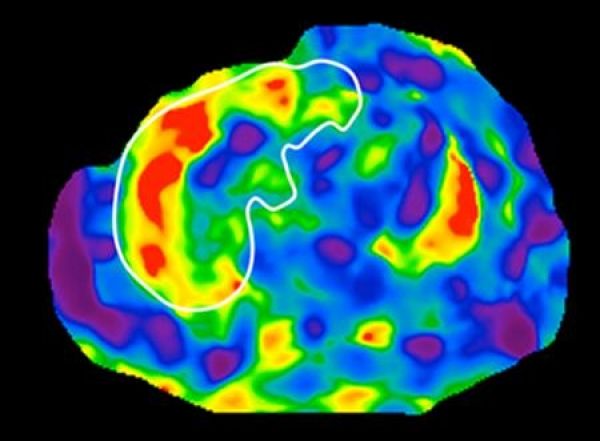

Image: Magnetic resonance elastography (MRE) scan of the liver showing elevated liver stiffness consistent with cirrhosis. MRE is a non-invasive, imaging-based biomarker for detection of cirrhosis. (Credit: UC San Diego Health)